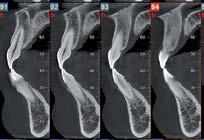

Se con la radiologia tradizionale era necessario eseguire scansioni multiple, la novità introdotta dal macchinario NewTom 5G XL risiede nella capacità di fornire immagini ad alta risoluzione in un’unica scansione, mostrando nitidamente i dettagli delle articolazioni degli arti superiori e inferiori. Inoltre, a differenza della tecnologia 2D, la radiologia 3D ortopedica permette di individuare immediatamente alcune patologie come quella del metatarso, la quale richiede un allineamento visivo dedicato o una diagnosi delle micro fratture ossee.